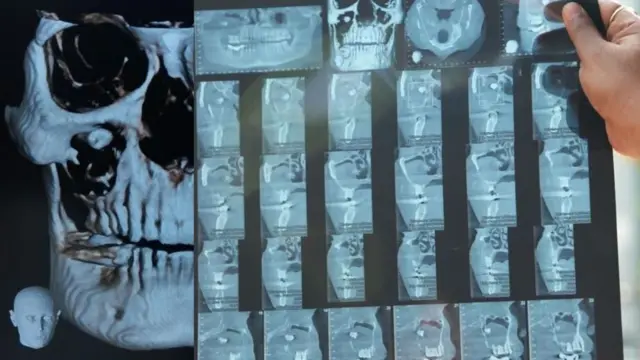

"મારું બધું કામ બંધ થતું જઈ રહ્યું હતું. જે બાદ મેં જૂનમાં આઇજીઆઇએમએસમાં દાંતના ડૉક્ટરને બતાવ્યું. ડૉક્ટરે મારો સીબીસીટી સ્કૅન કરાવ્યો. પછી ખબર પડી કે મારી આંખમાં તો દાંત છે. 11 ઑગસ્ટના રોજ ડૉક્ટરે મારું ઑપરેશન કર્યું. હવે હું સંપૂર્ણપણે સ્વસ્થ છું."

સીબીસીટી એટલે કે કોન બીમ કમ્પ્યૂટેડ ટોમોગ્રાફી. સરળ શબ્દોમાં આ એક પ્રકારનો ઍક્સ-રે છે. જે મૅક્સિલોફેશિયલ એરિયાનો ઍક્સ-રે કરીને થ્રી ડી તસવીરો બનાવે છે.

દર્દી રમેશકુમારે જ્યારે સીબીસીટી કરાયા બાદ ખબર પડી કે ફ્લોર ઑફ ધ ઑર્બિટમાં દાંતનાં મૂળ છે.

પ્રિયાંકર કહે છે કે, "આ મામલામાં દાંતનાં મૂળ ફ્લોર ઑર્બિટમાં હતાં. જ્યારે તેનો ક્રાઉન પોર્શન (દાંતનો સફેદ ભાગ) મૅક્સિલરી સાઇનસમાં હતો. આ દાંત પોતાની નૉર્મલ જગ્યાએ નહોતો બન્યો તેથી શરીર માટે એ ફૉરેન બૉડી હતો."

દાંત આંખના ફ્લોર ઑફ ધ ઑર્બિટમાં ઊગી રહ્યો હતો, તેથી જ્યાંથી ઘણી બધી નસો નીકળે છે, તેથી આ એક મુશ્કેલ સર્જરી હતી.